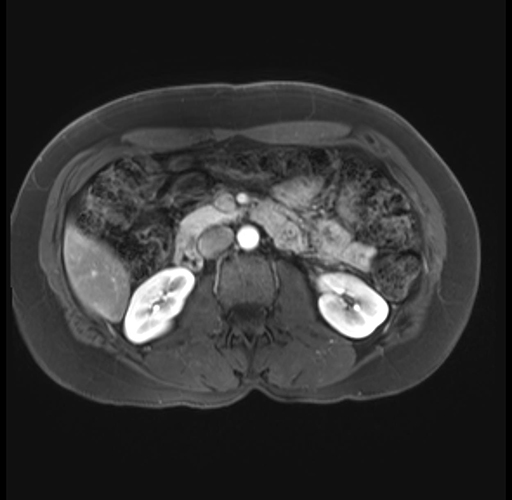

Imaging Analysis

Look through the patient's CT scan to identify any areas of concern for the necessary procedure.

Based on your CT findings, which issue(s) are present and would give reason for "planned slowing down moment(s)" in this case?